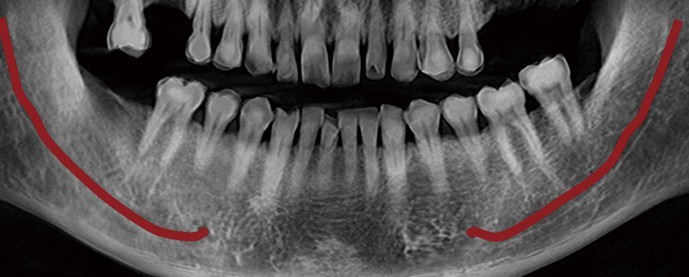

Arcada: Algoritmul AI generează automat linia arcadei în doar câteva secunde, cu o precizie ridicată.

Panorama cu autofocalizare și algoritm de reducere a zgomotului de imagine

Datorită tehnologiei multi-strat, Rainbow™ CT captează și segmentează automat cele mai bune imagini, pe care le compilează într-o singură panoramă optimizată. Algoritmul de reducere a zgomotului (De-Noising) asigură calitatea superioară a imaginii, eliminând interferențele și detaliile nedorite.

Panoramă cu autofocalizare

Algoritm de reducere al interferentelor (DE-NOISING)